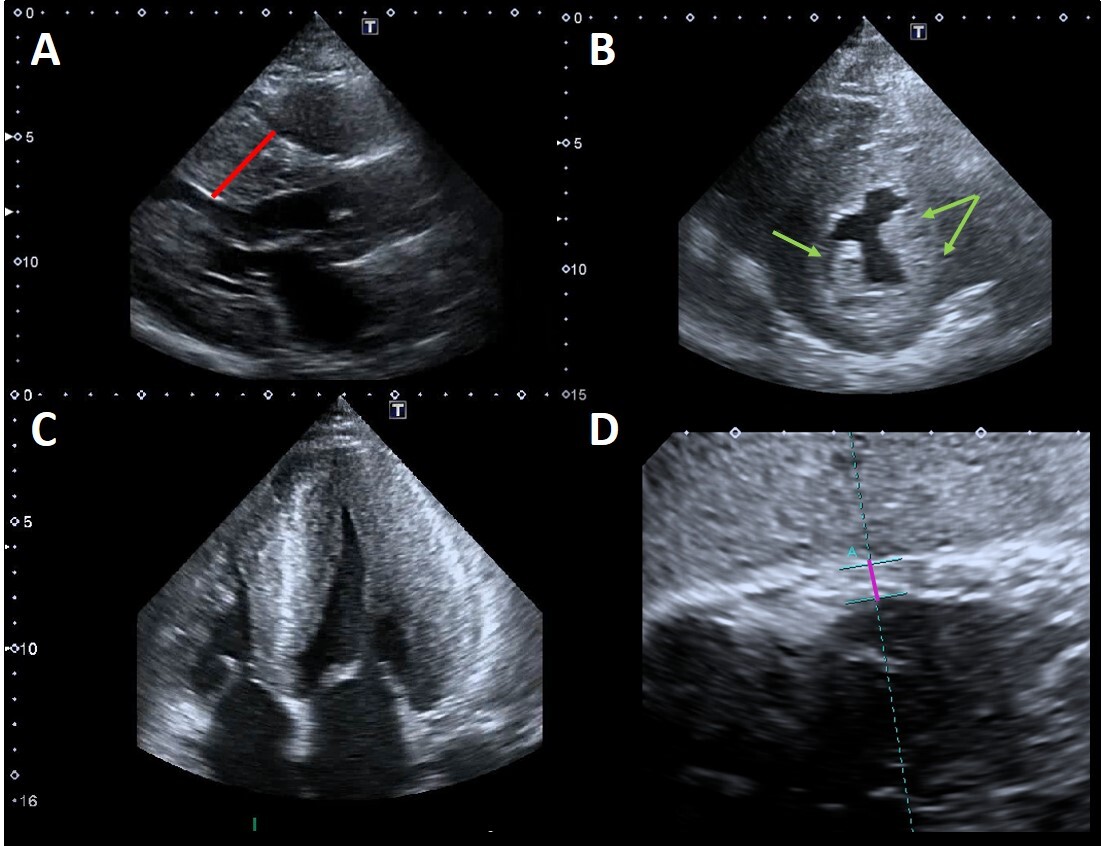

In FD, LVH is usually concentric [15] (Fig. 2A–C) but FC can also present with eccentric, apical [16], and asymmetric septal hypertrophy [17, 18, 19].

Fig. 2.Example of advanced Fabry cardiomyopathy. (A) Parasternal

long-axis view: the red line shows the maximal wall thickness (30 mm). (B)

Parasternal short-axis view: the green arrows point to the prominent hypertrophic

papillary muscles. The anterolateral papillary muscle is also bifid (double

arrow). (C) Apical four chambers view showing severe concentric LVH with reduced

LV cavity dimensions and moderate right ventricular hypertrophy. (D) Subcostal

view: the violet line shows the measurement of right ventricular wall thickness

(7 mm, n.v.

Papillary muscles hypertrophy and hyperechogenicity have been described in FD (Fig. 2A–C) and they might contribute not only to the increased LV mass but also to the development of mitral regurgitation. Niemann et al. [29] investigated the diagnostic value of this findings in a study on 101 consecutive patients with concentric LVH of various etiologies (FD, Friedreich ataxia, isolated arterial hypertension, amyloidosis) vs healthy control subjects. Enlarged absolute papillary muscle area was evidenced in 75%, and increased PM_LV_ratio (ratio of papillary muscle size to LV circumference) was found in 78% of 28 FD patients. Nevertheless, also this sign does not allow to certainly discriminate FD from other etiologies of LVH.

Right ventricular (RV) involvement is a common finding in FC (Fig. 2D). Prevalence of right ventricular hypertrophy (RVH) varies between 31% and 71% [66, 67] and its presence correlates with increasing age, disease severity and LVH. Kampmann et al. [66] found RVH in 46/129 patients (35.7%) and the 28.2% of them had severely depressed RV systolic function. On the contrary, Palecek et al. [68] found a prevalence of RV systolic dysfunction as low as 4.3% among FD patients with RVH. Accordingly, in a study on 45 FD patients, we found that RVH does not seem to significantly affect RV systolic function [69]. Even though RV TD systolic velocity values were slightly lower in patients with than in those without RVH, all parameters of RV systolic function were within the normal range. We also found that RV involvement parallels LV structural changes, being a feature of advanced disease, as supported by the fact that RVH was documented only in patients with concomitant LVH and was associated with LVMi and the Mainz severity score index. Moreover, when compared with patients with amyloid light chain cardiac amyloidosis with similar degree of RVH, patients with FC showed better RV systolic function.